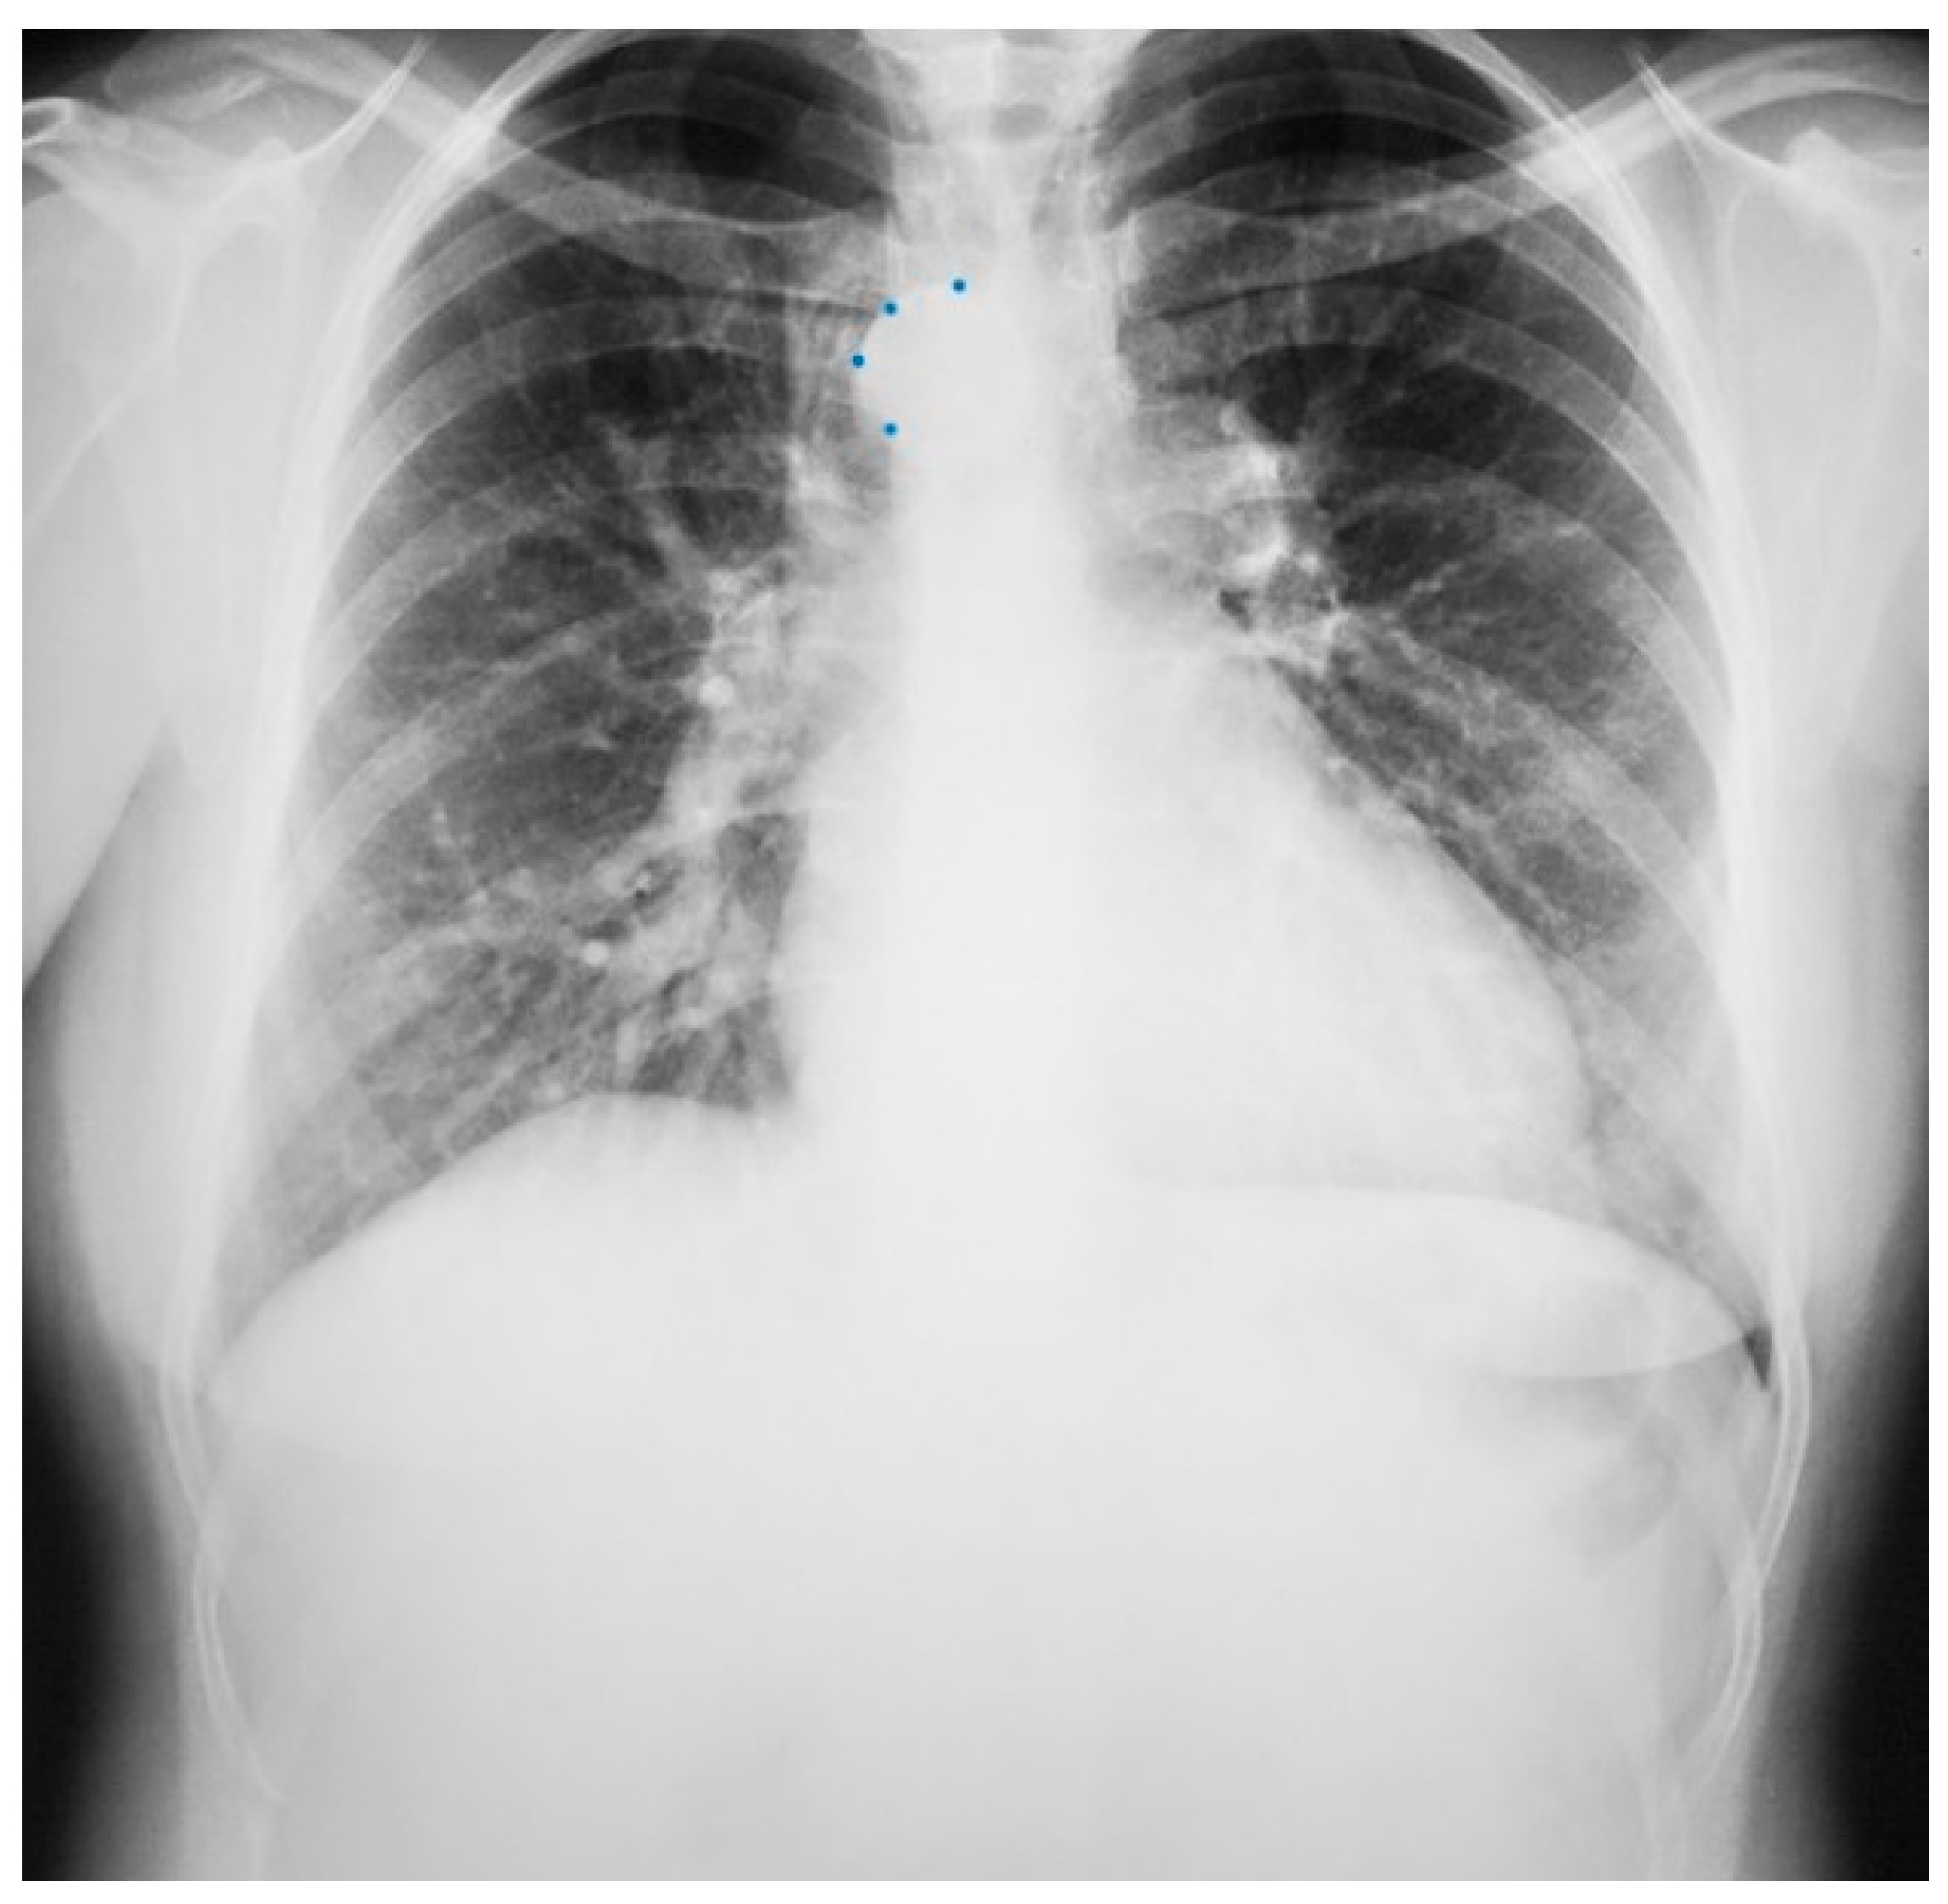

Figure 1.

Posteroanterior chest X-ray in congenital complete absence of the left portion of the parietal pericardium: A 30-year-old female was referred to a cardiologist because of an unusual chest X-ray done as part of an executive physical. She was asymptomatic and her vital signs and heart sounds were normal and there was no heart murmur or arrhythmia. The image is well centered, there is a good inspiration and the C-T ratio is <0.5. The heart is shifted into the left chest and the right heart border is obscured because it overlies the dorsal vertebral bodies. The pulmonary artery segment (outlined with blue dots) is enlarged but the pulmonary vascularity is normal, making left to right shunting unlikely. Echocardiography and Cardiac MRI confirmed she had CCALPPP. She was reassured. No treatment was necessary.